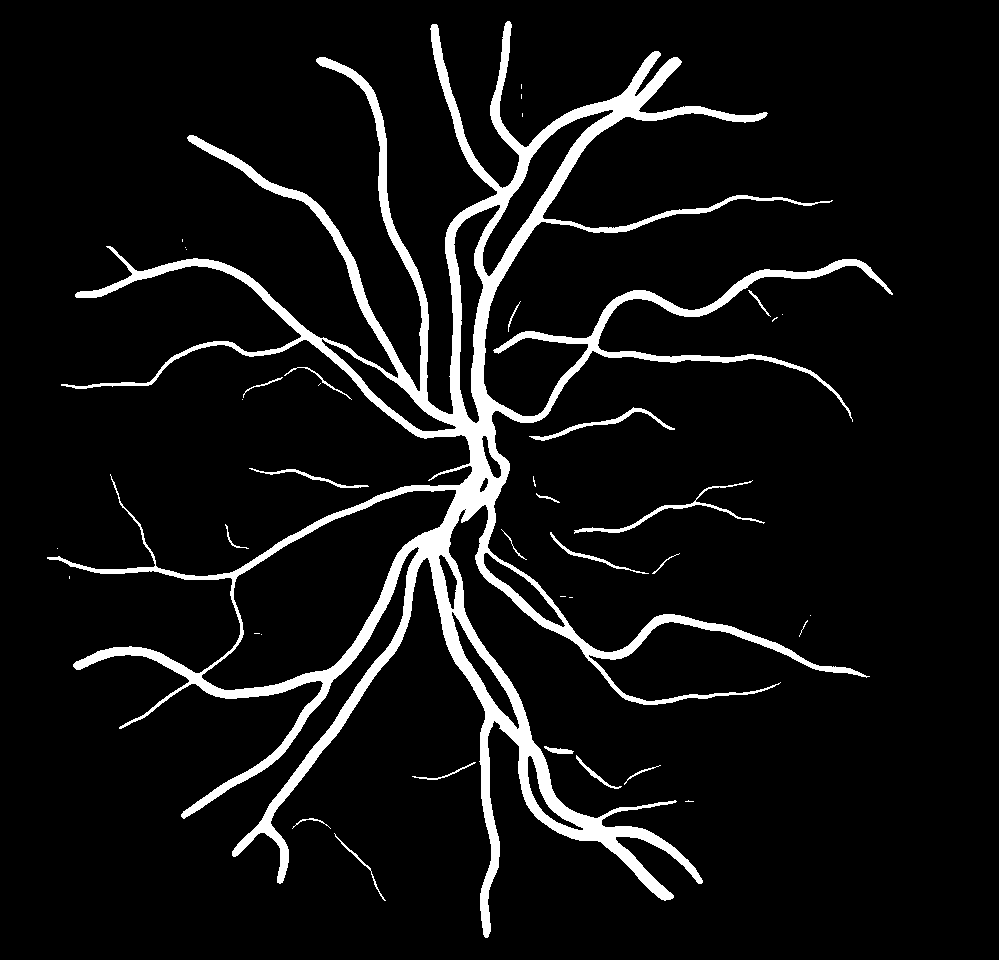

Using the final pretrained student SegRAVIR model in our knowledge distillation framework described in Section IV-D, we fine-tuned and tested the network on three publicly available datasets of color images, DRIVE [10], STARE [9], and CHASE_DB1 [12]. Fig. 7 shows example of SegRAVIR segmentation outputs on DRIVE and CHASE_DB1 datasets. Table VII presents a quantitative comparison between the segmentation performance of our SegRAVIR model and state-of-the-art models: R2U-Net [25], DU-Net [26], and IterNet [34]. By all evaluation metrics, SegRAVIR has achieved new state-of-the-art results on the DRIVE, STARE [9], and CHASE_DB1 datasets.